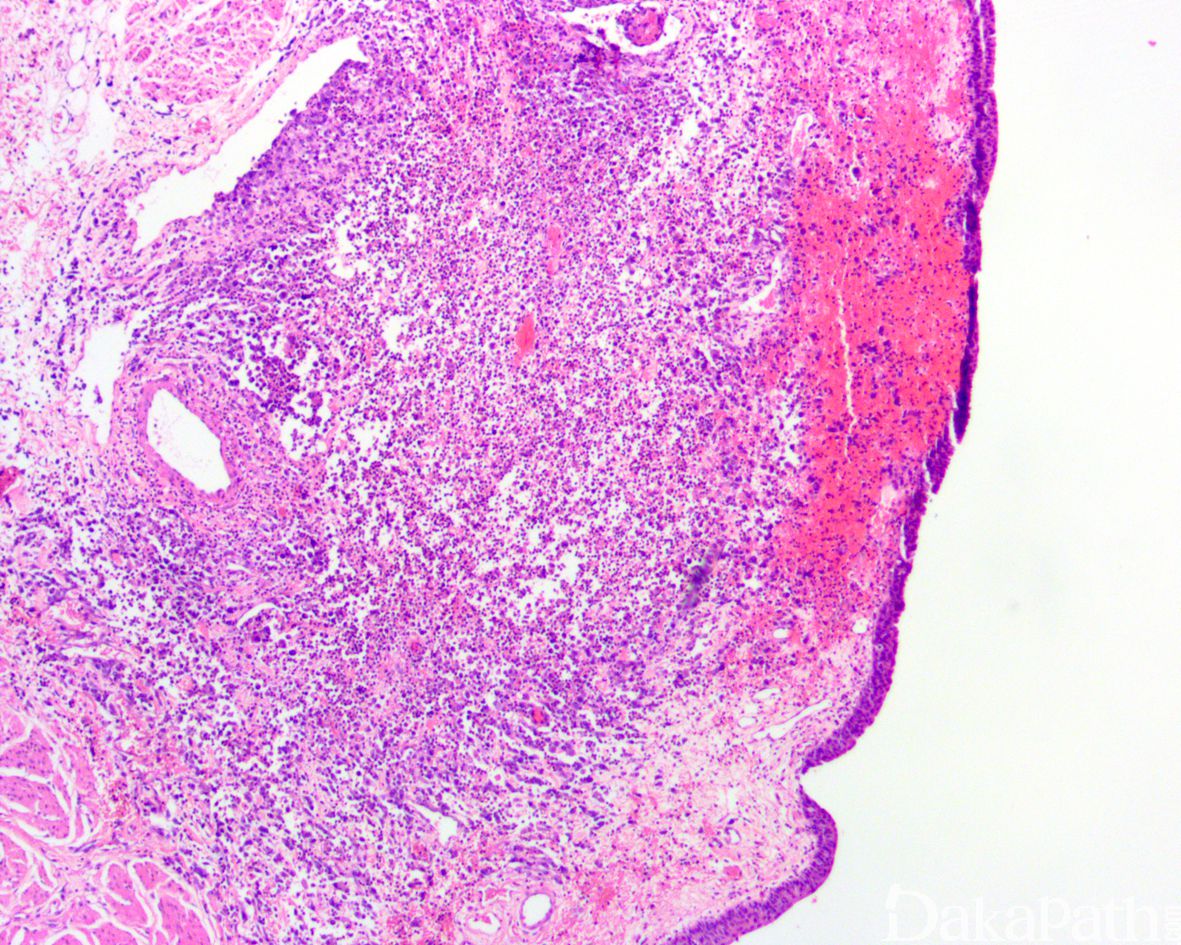

罕见,占所有尿路上皮癌的比例不超过 5%;大体上表现为单发或多发性肿块,弥漫浸润膀胱壁使膀胱增厚,产生类似于皮革胃样的大体表现;

部分病例可见原位尿路上皮癌或乳头状尿路上皮癌,部分病例的表面黏膜可完全正常;

常见脉管内癌栓。浆细胞样尿路上皮癌可沿着筋膜播散并浸润至腹膜,因此应对肿瘤进行广泛的取材。